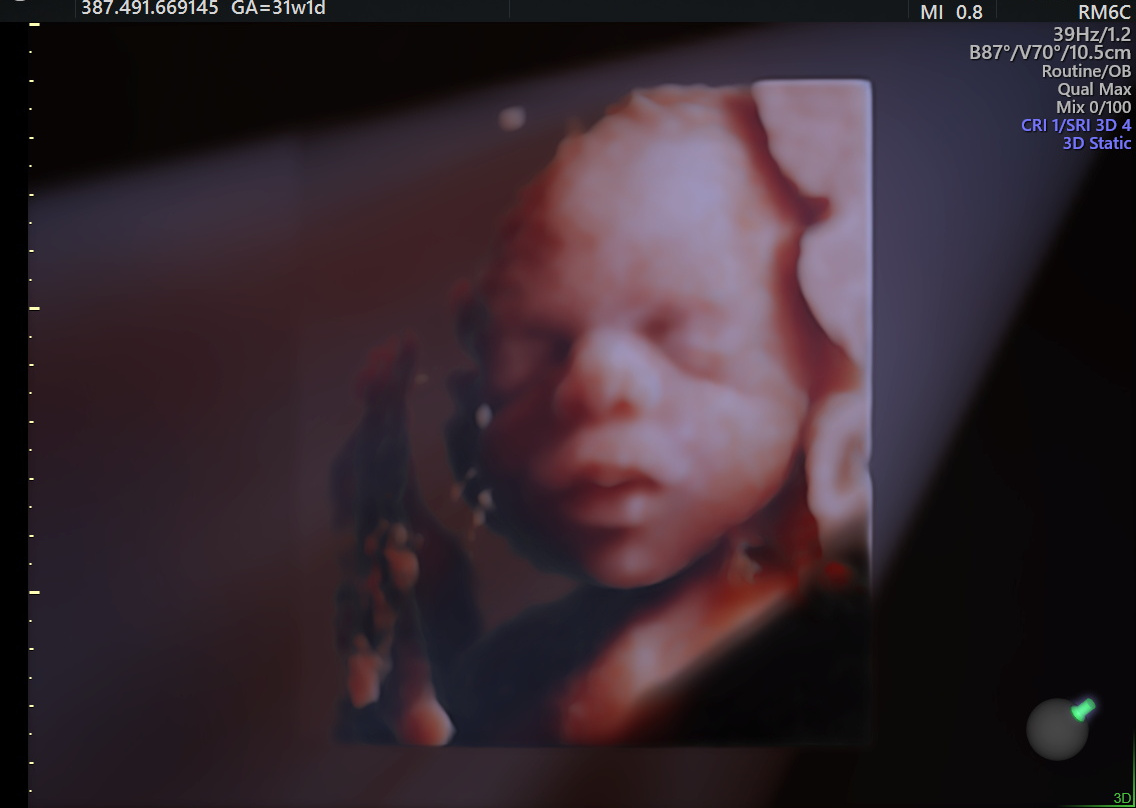

Développement du fœtus 31 semaines de grossesse Votre bébé pèse environ 3,3 lb (1,5 kg) et mesure à peu près 41 centimètres de la tête aux orteils Il commence à ressembler à un nouveauné Enfin proportionnés par rapport à sa tête, ses bras, ses jambes et son corps continuent leur croissance Vous avez peutêtre remarqué 3 WEEKS Twins implantation Nonidentical twins like these (also known as dizygotic twins) are the most common Each baby grows from a separate fertilized egg (zygote) By 3 weeks each zygote has developed into a ball of several hundred cells, called a blastocyst, and is burrowing into the uterine lining See a bigger picture Le site des futures mamans clouées à leur canapé !

The underdeveloped brain of baby born at 31 weeks may cause apnea (loss of breathing) that subsides as the baby grows and usually doesn't require long term treatment/medications 2 Feeding Problems Some preterm babies are unable to suckle effectively while others are unable to tolerate and digest breast milkVotre bébé à 29 semaines de grossesse (31 SA) Au cours de cette 31 ème semaine d'aménorrhée, le fœtus continue de grossir et grandir tranquillement Il se sent de plus en plus à l'étroit Même s'il est moins mobile, Il bouge beaucoup et de façon plus vigoureuse Vous ressentez ses1,8kg et 42 cm poids estimé a terme 3,2kg et 50cma suivre car je vois que l'une de vous a le mm poids a 31sa et pas la mm estimation a terme J'aime à 23h21 31sa 6 Loulou mesurerait 40cm pour 10g ( ou 10%) Bien dans les courbes Poids estimé à la naissance 3600g